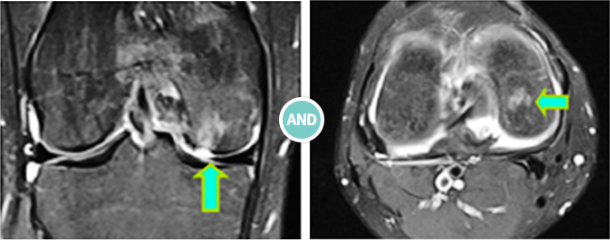

무릎관절은 세 개의 관절 면으로 구성되어 있는데 각종 질환, 외상 등으로 제 기능을 수행하지 못할 때,

관절면을 절제, 제거하고 생체조직의 거부반응이 적고 관절면의 기능을 원활하게 수행할 수 있는

대체물질(인공관절)로 전환하는 치료법입니다.

인공관절 치환을 통해 통증을 감소시키고 관절의 기능을 유지시키고 변형을 고정하여 일상생활이 가능하도록 합니다.